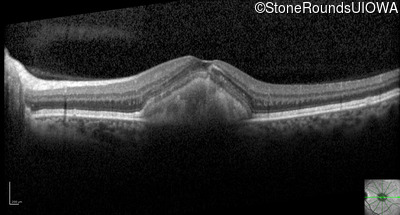

Optical Coherence Tomography - Right - 20/40 -1

Exemplar / OCT Stack